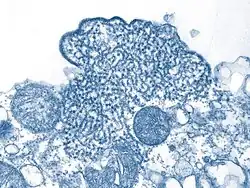

Transmission electron micrograph (TEM) depicted a number of Nipah virus virions from a person's cerebrospinal fluid (CSF).

During acute and convalescent stages of the disease, RNA can be detected using reverse transcriptase polymerase chain reaction (RT-PCR) from throat swabs, cerebrospinal fluid, urine and blood analysis.[1]

After recovery, IgG and IgM antibody detection can confirm a prior Nipah virus infection. Immunohistochemistry on tissues collected during autopsy also confirms the disease.[1]